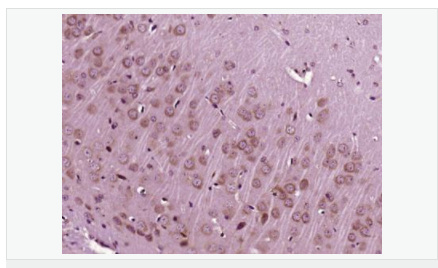

| 產品應用 | WB=1:500-2000 ELISA=1:5000-10000 IP=1:20-100 IHC-P=1:100-500 IHC-F=1:100-500 IF=1:100-500 (石蠟切片需做抗原修復) not yet tested in other applications. optimal dilutions/concentrations should be determined by the end user. |

| 免 疫 原 | KLH conjugated synthetic peptide derived from human IGF-1:49-100/195 |